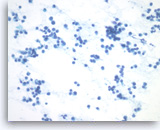

Pancreatic endocrine neoplasm #1,

Pancreas FNA, Direct Smear.

The aspirates show single and dyshesive clusters of neoplastic cells. The neoplastic cells show mild variation in size and have eccentrically located oval nuclei (plasmacytoid appearance). A few small cytoplasmic vacuoles are seen.

40X

Pancreatic endocrine neoplasm #1,

Pancreas FNA, Direct Smear.

The aspirates show single and dyshesive clusters of neoplastic cells. The neoplastic cells show mild variation in size and have eccentrically located oval nuclei (plasmacytoid appearance). A few small cytoplasmic vacuoles are seen.

40X

Pancreatic endocrine neoplasm #1,

Pancreas FNA, Direct Smear.

Dispersed dyshesive neoplastic cells have speckled (“salt and pepper”) chromatin and inconspicuous nucleoli.

40X

Pancreatic endocrine neoplasm #1,

Pancreas FNA, Direct Smear.

Dispersed dyshesive neoplastic cells have speckled (“salt and pepper”) chromatin and inconspicuous nucleoli.

40X

Pancreatic endocrine neoplasm #1,

Pancreas FNA, Cell Block.

The tumor cells are present singly or in sheets and groups without a crisp, normal acinar arrangement.

40X

Pancreatic endocrine neoplasm #1,

Pancreas FNA, Cell Block.

The tumor cells are present singly or in sheets and groups without a crisp, normal acinar arrangement.

40X